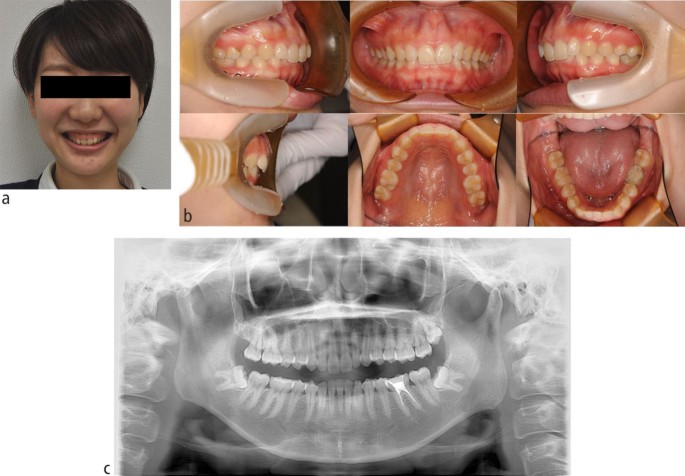

For orthodontic treatment, 0.018-inch standard edgewise brackets were bonded on the maxillary teeth. Two self-drilling TADs (diameter, 1.6 mm; length, 8 mm; Dual Top Auto Screw; Jeil Medical Corp, South Korea) were inserted into the buccal alveolar bone between the maxillary lateral incisors and canines to intrude the maxillary anterior teeth using an elastic chain. Before completion of opening the bite, positive crown torque of the upper incisors was achieved by torque moment generated with intruded force (Fig. 2A). After opening the bite, brackets were bonded on the mandibular teeth to create space between mandibular right central incisor and canine. However, after 12 months of intrusion, the crown of the maxillary right central incisor showed grey discoloration and a negative response to electric pulp tests (Fig. 2B). Furthermore, the patient reported severe spontaneous pain only in this tooth two days before visiting our clinic. However, no significant radiographic change was observed around the root apex of the maxillary right central incisor. Notably, moderate apical root resorption was observed in the maxillary right lateral incisor by the dental x-ray (Fig. 2C). From these symptoms, we thought traumatic pulp injury occurred on the right central incisor. Therefore, we removed the orthodontic force on the maxillary incisors with passive wire ligations between TADs and the upper canines, and 60 mg of loxoprofen sodium was administered three times a day for seven days. No more intrusion force to the upper incisors was applied because opening the bite had been completed. Six months after stopping orthodontic treatment, resolution of the crown discoloration was observed and the response to electric pulp testing was restored (Fig. 3A). Periapical radiography revealed a distinct radiolucency at the root apex (Fig. 3B). Two years after initiation of orthodontic treatment, the patient's gummy smile and overbite were corrected with a good intercuspal relationship. The missing mandibular right lateral incisor was replaced by direct bonding (Fig. 4A, Fig. 4B). Follow-up at four years after beginning of retention revealed stable smile aesthetics and tooth positions (Fig. 4C, Fig. 4D). Periapical radiographs showed marked root canal obliteration in the maxillary right central incisor and remodelling of the root apex in the maxillary right lateral incisor (Fig. 4E). The wire sequence used in this case is shown in Table 1.

(A) Intrusion of the maxillary anterior teeth using an elastic chain from temporary anchorage devices. (B) Intra-oral photograph 12 months after anterior teeth intrusion. The crown of the maxillary right central incisor showed discoloration. (C) Dental x-ray immediately after discoloration of the crown